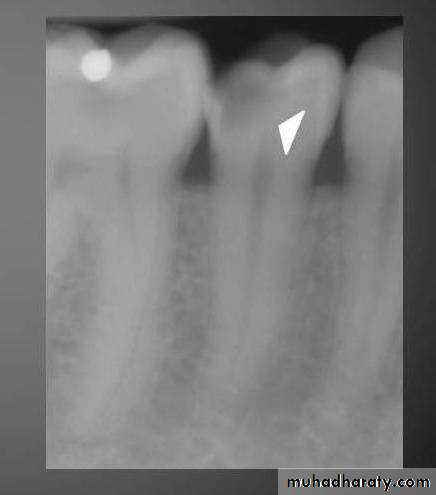

Radiograph of buccal or lingual caries. Buccal or lingual caries on this mandibular second premolar appears as a round radiolucency (superimposed over the pulp chamber)